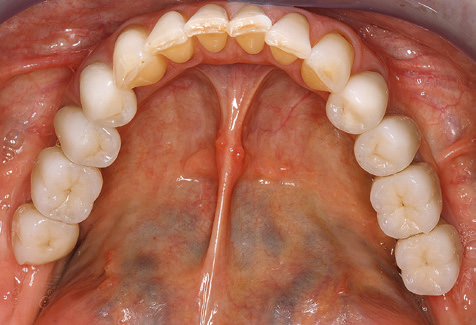

Description of patient case

A 52-year-old patient presented in our clinic for the first time in 2004 following tooth loss in the third quadrant, expressing a desire for a new prosthetic restoration. Periodontal and radiological diagnostics revealed the need for extensive periodontological treatment. In addition, teeth 48, 28 and 27 were attributed a very poor prognosis and were subsequently extracted (Fig. 1). Following the successfully completed, systematic periodontological treatment, a fixed dental implant was inserted with the introduction of five implants in tooth regions 35, 36, 37, 46 and 47. Prosthetic treatment of the natural teeth was effected with veneered zirconium dioxide ceramic crowns; the implants were composed of two-piece, individual zirconium dioxide abutments and similarly veneered crowns made of a zirconium dioxide ceramic (Cercon base colored, Dentsply Sirona Lab). Definitive insertion of the prosthetic restoration occurred in 2005.